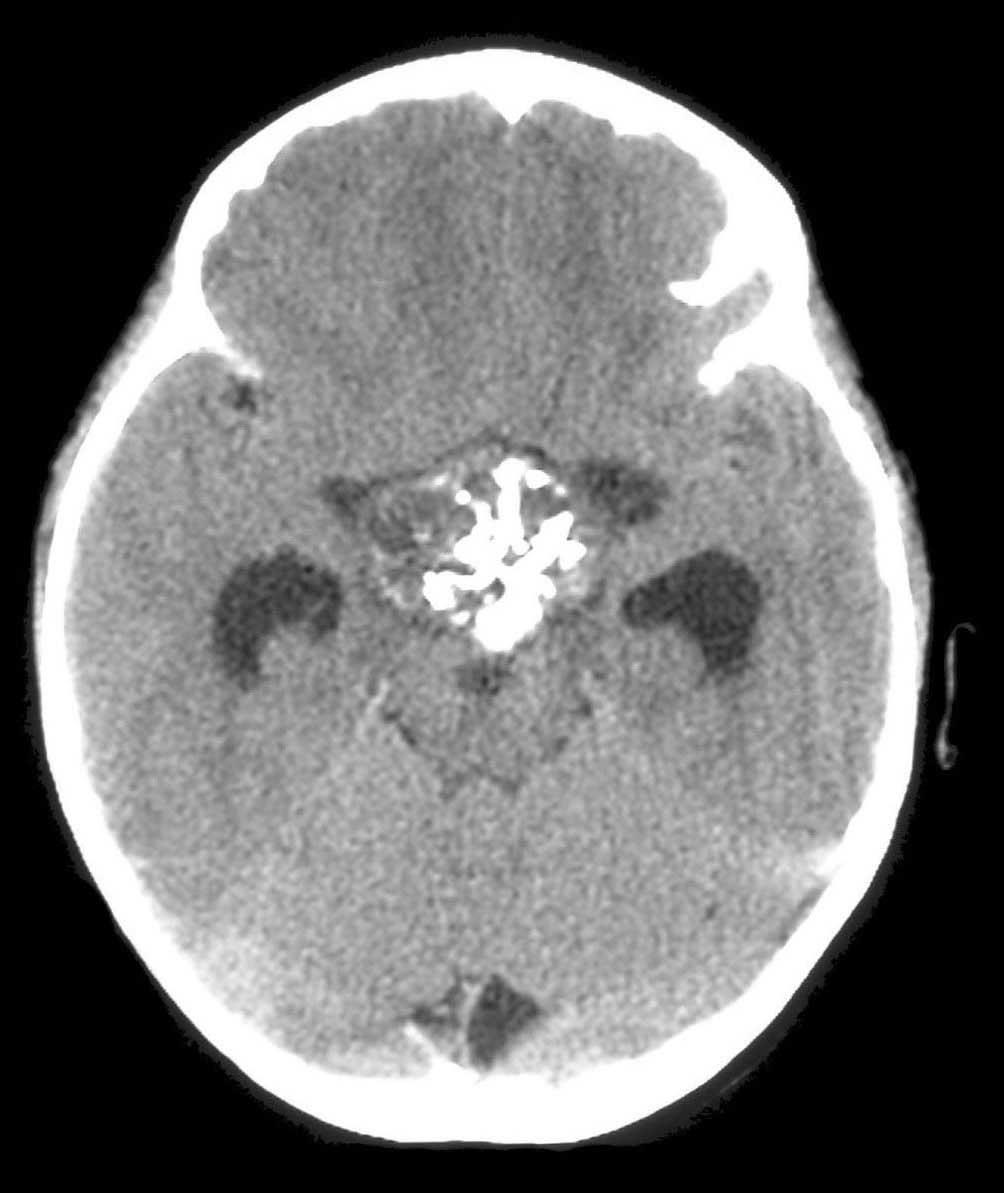

A 73-year-old woman is brought to the hospital with increasing confusion, gait deterioration, and headache. Physical examination reveals a contusion over the left temporal region. Her pulse is 109/min and blood pressure is 132/84 mm Hg. Pupils are 3 mm, round, and reactive. Neurologic examination reveals slurred speech and right-sided weakness. A noncontrast CT scan of the head is shown.

Which of the following structures is most likely abnormal or damaged in this patient?

B) Bridging veins

SDHs may result from blunt trauma and appear as a crescent-shaped area of bleeding on brain CT scan. SDHs occur due to shearing of bridging veins.